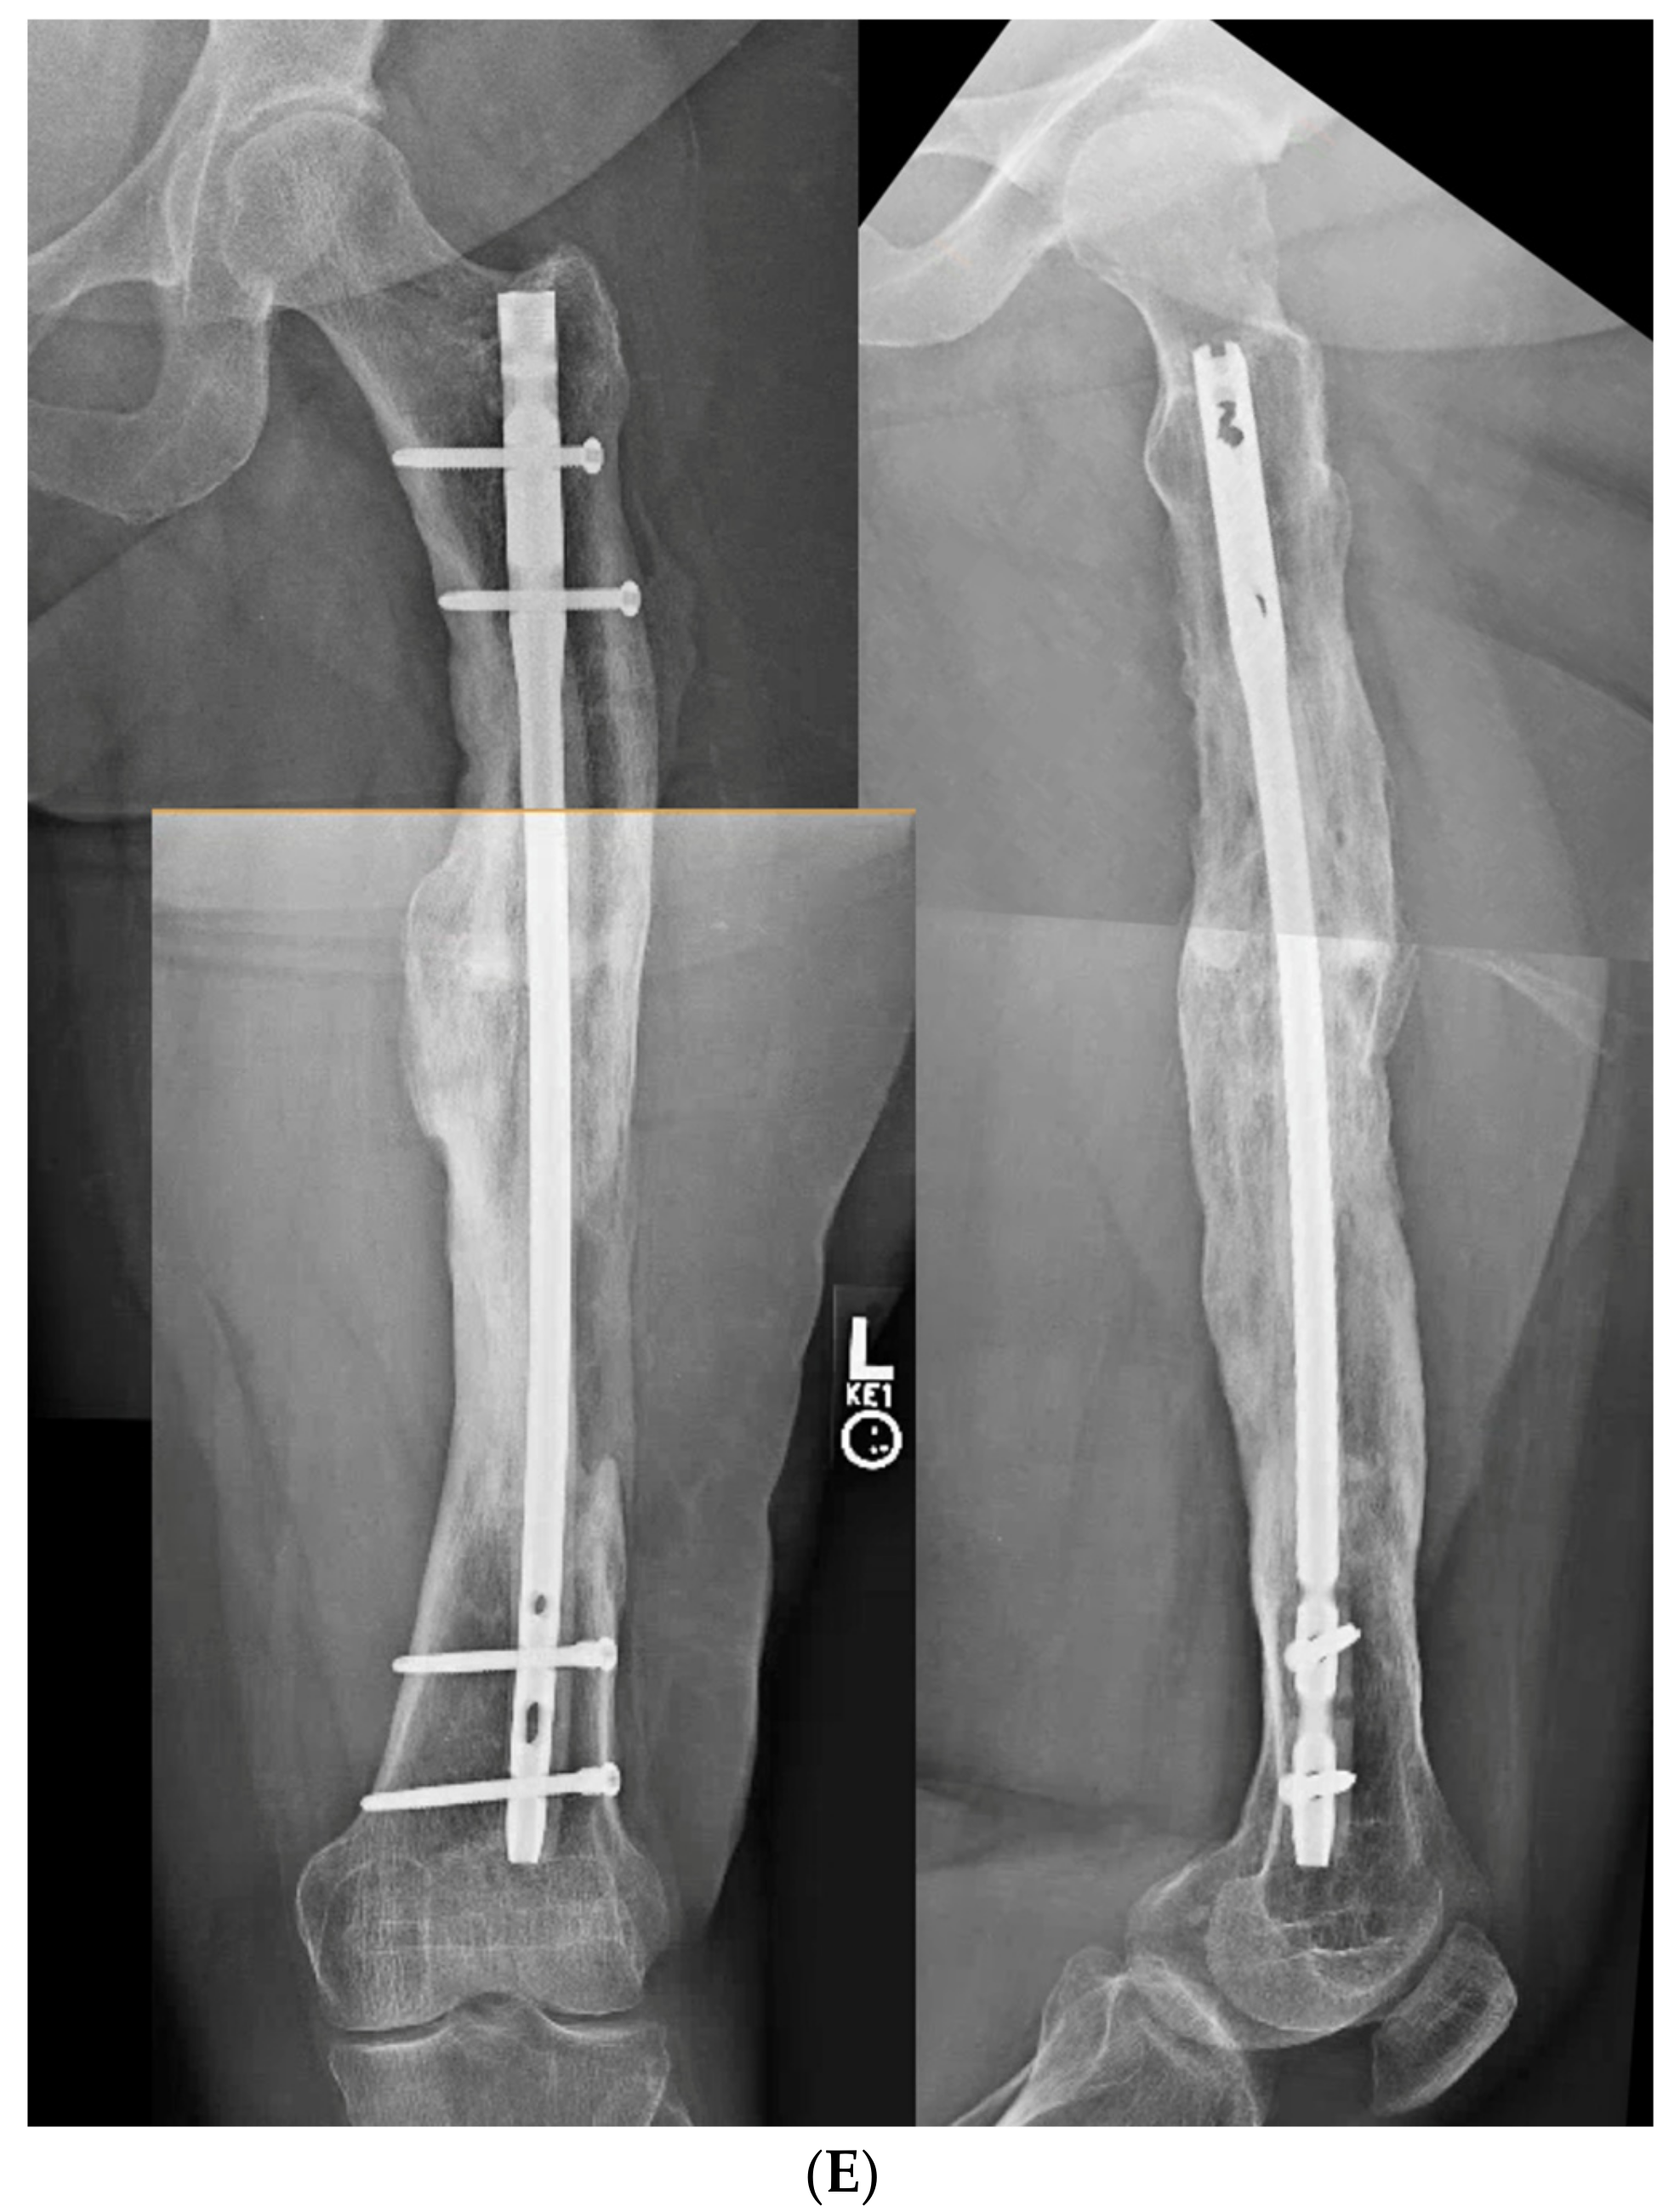

3.2. Case 2-Single-Plane Correction with Plate Fixation: Tibia

A young adult college baseball player presented with symptoms of lateral proximal knee pain and a feeling of knee instability 8 months after sustaining a closed fracture of the tibia, initially treated closed with casting (Figure 7A). The patient underwent a workup including full-length films, knee MRI, and local anesthetic test injection of the proximal tibiofibular joint (relieving knee pain). The CORA analysis revealed a recurvatum deformity of 10 degrees and varus deformity of 3 degrees, with translation in the coronal plane. Full-length alignment film of the pelvis and lower extremity confirmed coronal translation with mild varus angulation (Figure 7B). The true plane of deformity was calculated approximately 75 degrees from the coronal plane (15 degrees off-sagittal) with a magnitude of between 10 and 11 degrees.

Figure 7.

(A) A young adult college baseball player sustained a closed tibia fracture with intact fibula, treated closed. The patient developed a recurvatum deformity with pain at the proximal and distal tibiofibular joints. (B) The patient demonstrated mechanical axis lateralization due to coronal plane translation with slight varus. The plane of deformity was calculated as 73 degrees off of the coronal plane. (C) The patient underwent focal dome osteotomy at the CORA (yellow circle) in the plane of maximum deformity. (D) Dual plate compression was used. Angulation and translation were simultaneously corrected. (E) Final follow-up 9 months: anteroposterior, lateral, and oblique films show the osteotomy healed. Tibiofibular joint pain resolved after osteotomy. Patient returned to college-level baseball.

A focal dome was chosen to correct the varus recurvatum and translation. The surgical approach was an anterior approach over the anterior compartment, elevating the tibialis anterior from the lateral tibia to allow safe access to the plane of the deformity. The fibula was osteotomized near the level of the tibia through a separate lateral approach. The plane of maximum deformity was assessed intraoperatively and confirmed the preoperative calculations. The ‘no deformity’ view on fluoroscopy was located, with the maximum plane orthogonal to this. It is in this plane that the drill bit at the CORA is directed, and this is especially important if correcting a translation. The arc of the osteotomy was drawn using a parallel drill guide with one bit centered at the CORA (Figure 7C).

The angulation and translation were simultaneously corrected. Dual medial–lateral plates were used to counteract the lateral gap forming with medial plate compression. Hence, balanced compression from the medial and lateral plates restored the alignment and provided absolute stability (Figure 7D). The patient had immediate relief of knee pain after correction. The soft tissue and osteotomy healed without incident (Figure 7E).